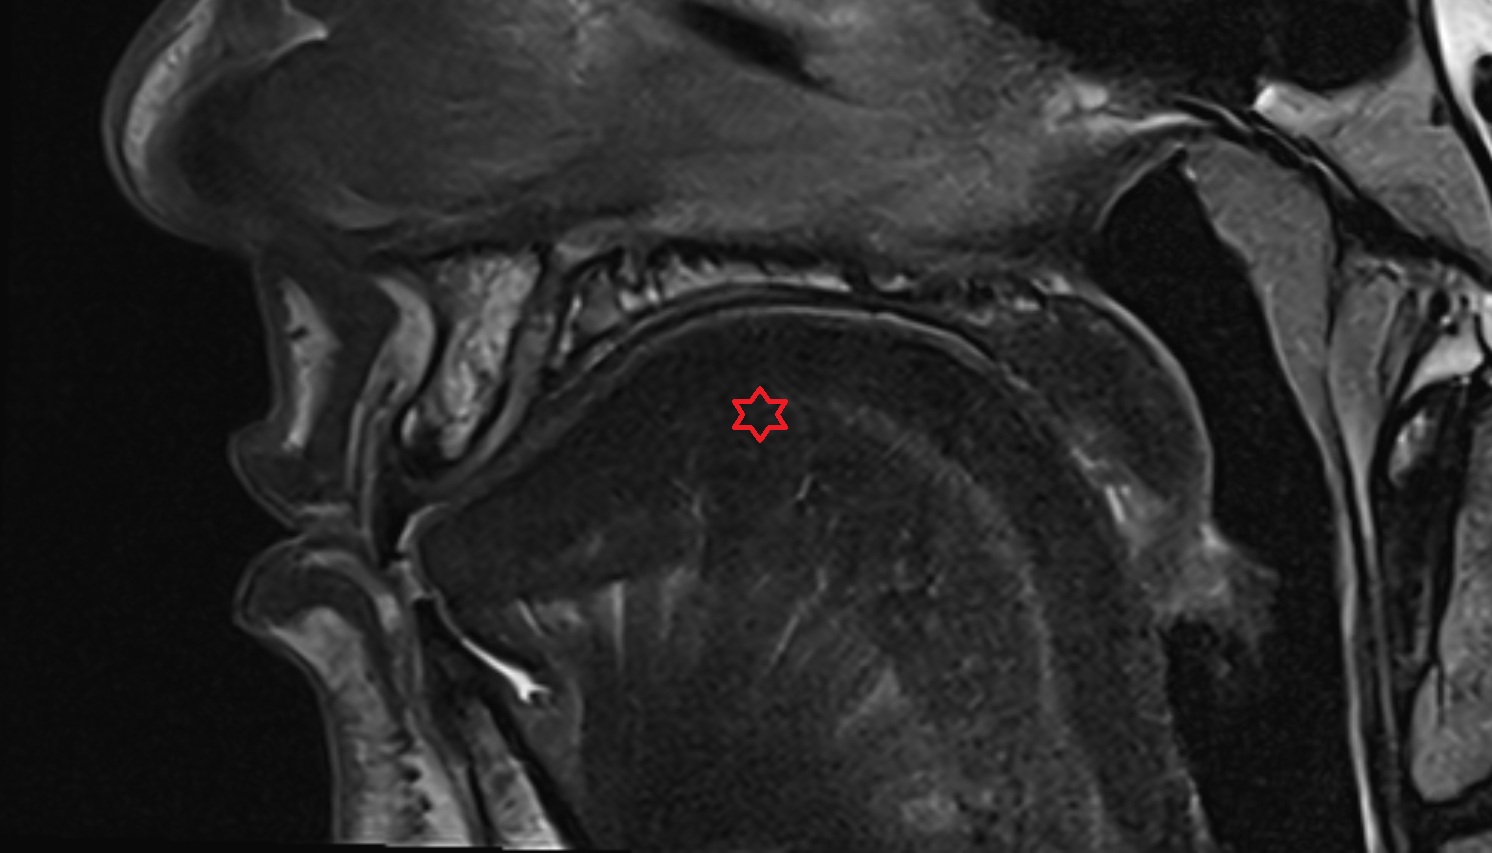

- Peripheral zone of prostate

- Anterior Fibromuscular Stroma of prostate

- Central zone of prostate

- Transitional zone of prostate